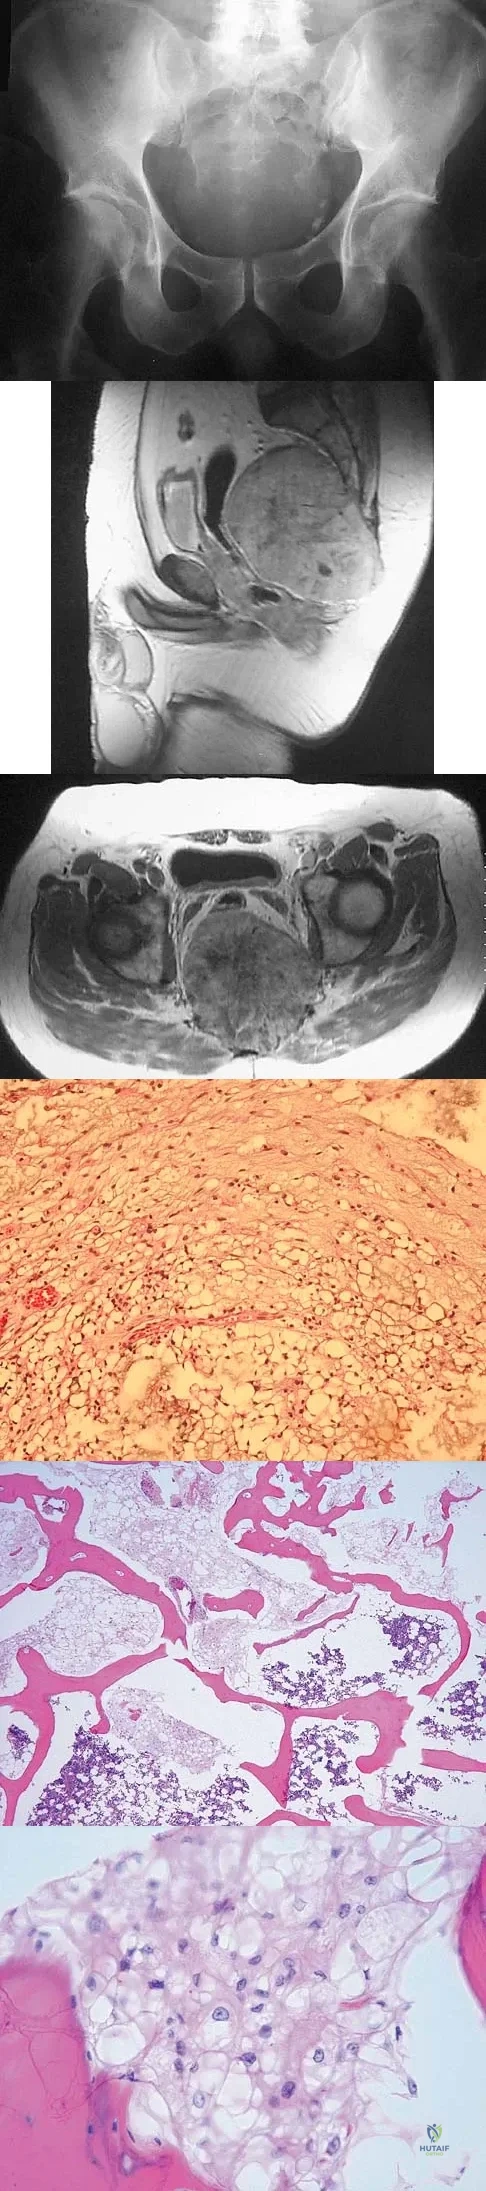

A 62-year-old woman reports diffuse aches and pains of the hip and pelvis. She denies any significant trauma but does have a history of chronic anemia. Figure 17a shows a radiograph of the pelvis, and Figures 17b and 17c show T2-weighted MRI scans. What is the most likely diagnosis?

Explanation